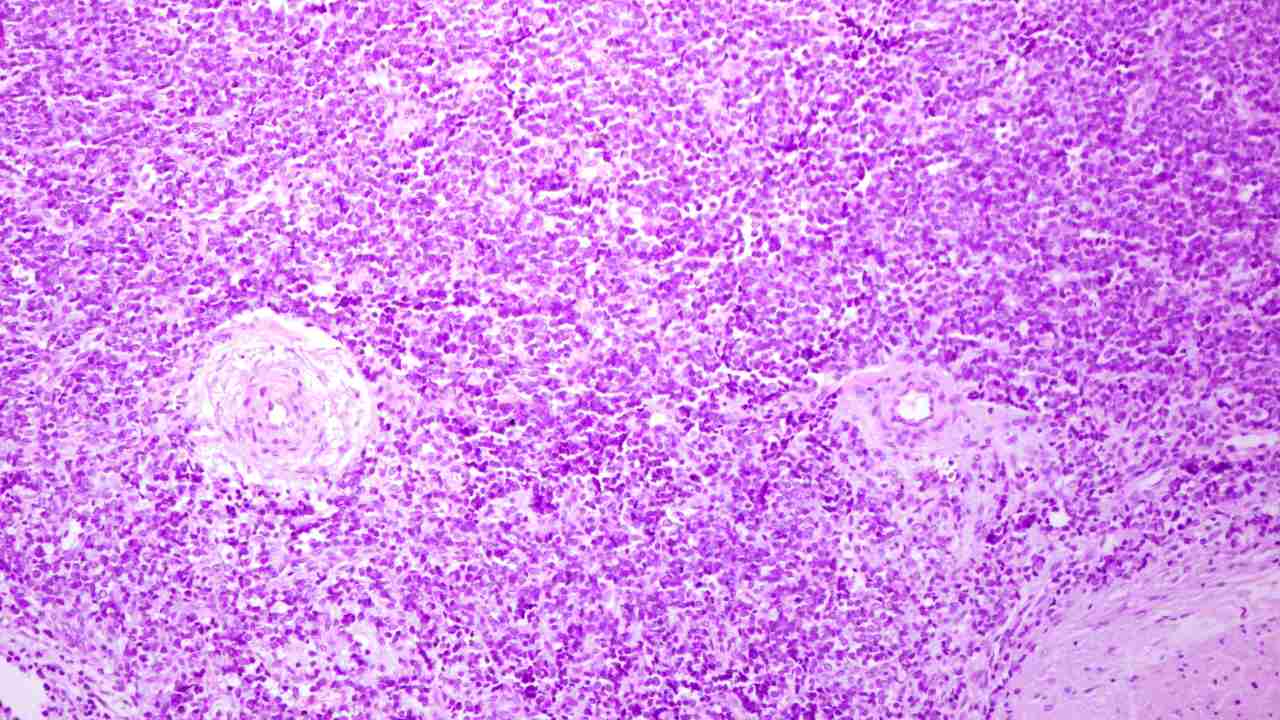

Imagen: ©Shutterstock / Jose Luis Calvo